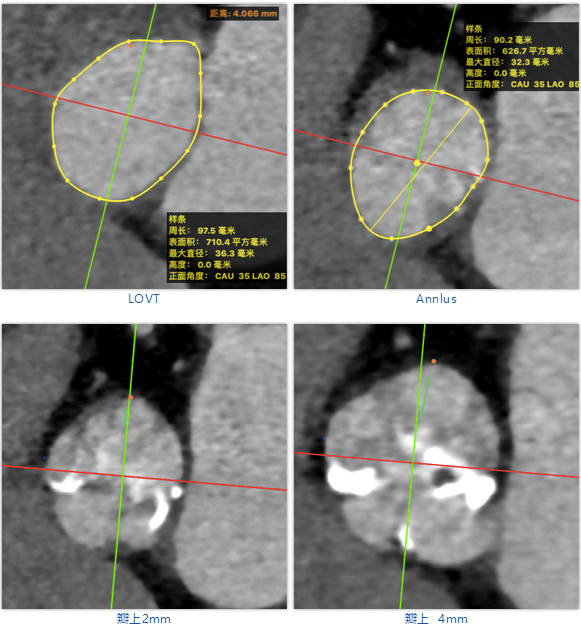

患者为74岁男性,升主动脉增宽,主动脉瓣叶及瓣环明显钙化,中重度狭窄。

主动脉瓣中重度狭窄,主动脉瓣叶及瓣环明显钙化,主动脉瓣PGmean:63mmHg、Vmax:4.0m/s,LVEF:61%,二尖瓣少量反流轻度关闭不全,三尖瓣轻中度关闭不全。

武汉协和董念国团队对该病例进行了缜密探讨,该病例为老年男性,主动脉瓣中重度狭窄,术前左室舒张功能减低。患者病例CT和心超数据显示瓣环瓣周长:90.2mm,瓣下4mm流出道周长:97.5mm,窦部空间相对小,单纯无冠瓣瓣叶钙化,三叶瓣。左冠风险较高,缜密分析瓣叶遮盖率>50%,术中可能存在阻挡风险,需要术中球囊扩张时仔细辨认,并准备冠脉保护策略。综合评估考虑右股动脉更适宜为主入路。经过团队严谨的评估及充分的讨论,决定先行25mm球囊预扩并进一步确认冠脉风险,并准备TAV29和TAV32规格的ProStyle预装式可回收TAVR系统。